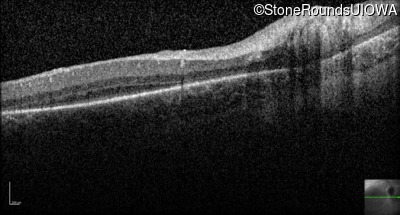

Optical Coherence Tomography - Right -

No Light Perception

Optical Coherence Tomography - Left -